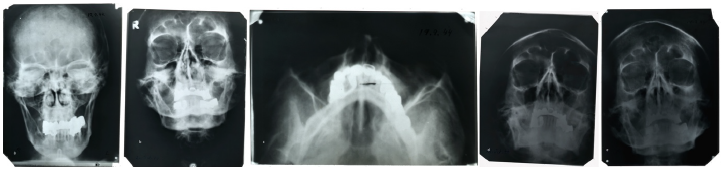

Второй образец, точнее, группа образцов из архива ФСБ (бывшего архива КГБ), представляет собой фрагмент верхней и три фрагмента нижней челюсти с зубами и коронками. Исследователи провели визуальное исследование костей и зубов под бинокуляром, элементный анализ костей и анализ поверхности зубов при помощи электронной микроскопии. Кроме того, в распоряжении экспертов оказались рентгеновские снимки головы, сделанные Гитлером в 1944 году, которые ранее хранились в США. Как видно на снимках, у него сохранилось только четыре целых собственных зуба (нижние резцы). Оказавшиеся у ученых фрагменты челюстей действительно содержали целые нижние резцы, а почти все остальные зубы были с металлическими коронками.

Рентгеновские снимки Адольфа Гитлера, сделанные в 1944 году, фото: P. Charlier et al / European Journal of Internal Medicine 2018